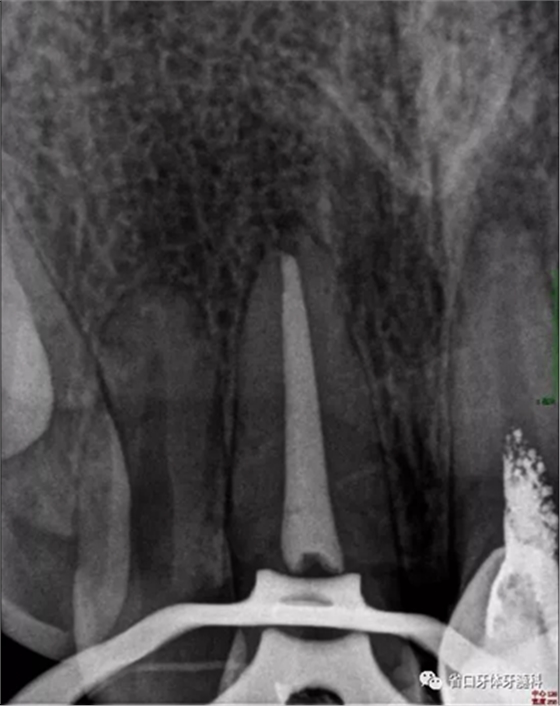

2周后復診:封藥存,患牙無不適,叩痛-,齦無紅腫。去封藥,清理根管,試主尖到位,沖洗、干燥,熱牙膠充填至釉牙骨質(zhì)界下2mm,照片顯示恰充。

圖5 根充片